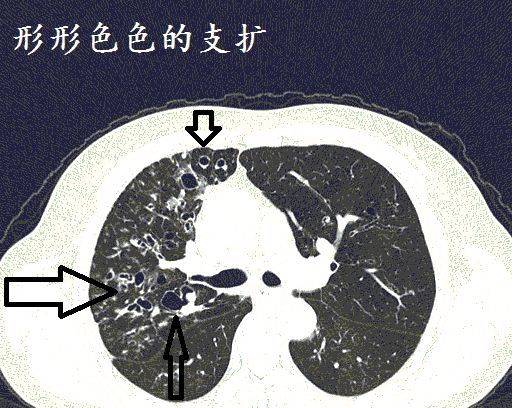

经典图谱,详细解说支气管扩张ct小诀窍!学不会我拜你为师!

手把手教你支气管扩张ct诊断

支气管扩张症影像表现